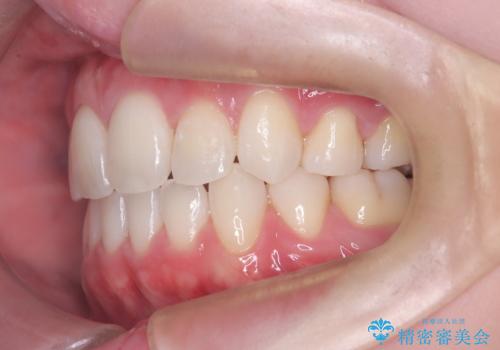

上下4本の抜歯と審美ワイヤー矯正で整った歯並びへ

- 患者様は、歯並びの乱れを整えたいとのことで来院されました。診察の結果、歯列のスペース不足が原因で前歯のガタつきが目立ち、噛み合わせにも影響が出ている状態でした。歯を正しく並べるためにはスペースの確保が必要と判断し、上下の小臼歯4本を抜歯して、審美ワイヤー矯正(白いワイヤーと透明ブラケット)で治療を行う計画を立てました。

まず、抜歯によって歯を動かすためのスペースを確保。その後、審美ワイヤー矯正を用いて、前歯のガタつきを整えながら、噛み合わせの調整も行いました。審美装置を使用することで、矯正中も目立ちにくく、自然な仕上がりを目指して治療を進めました。治療の結果、歯並びがきれいに整い、口元のバランスも改善しました。患者様からは「歯並びがきれいになり、自信を持って笑えるようになった」と喜びの声をいただきました。